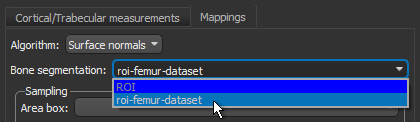

- Do the following on the Mappings tab:

- Choose Surface normals in the Algorithm drop-down menu.

- Choose the region of interest that you created for this tutorial in the Bone segmentation drop-down menu.

- Choose the box that encloses the area that you want to include in your analysis in the Area box drop-down menu.

- Enter a value of 0.002 m in the Spacing edit box.

- Select a value between 1 and 3 mm in the Radius of influence edit box.

- Choose Projection-based in the Anisotropy drop-down menu.

- Choose a number of iterations in the Mesh smoothing (repetitions) spin box, optional.

- Click the Compute Mapping button.